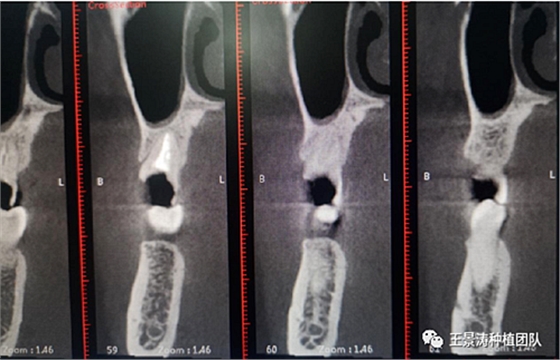

下述病例則是15區(qū)域的即刻種植,15因牙冠折斷于齦下,無法樁核冠修復(fù),則考慮種植修復(fù)。但拍攝CBCT后發(fā)現(xiàn)根尖距上頜竇底距離較短?;颊邽槟贻p女性,無全身系統(tǒng)疾病且可利用上頜竇底與根尖皮質(zhì)骨雙側(cè)皮質(zhì)骨固位,且此位置可通過頰側(cè)軟組織減張技術(shù)獲得嚴(yán)密封閉牙槽窩。因其根尖距上頜竇距離較低,遂拔除15后行上頜竇內(nèi)提升,埋入式種植,最終修復(fù)的完成。

左側(cè)下頜第二磨牙及右側(cè)下頜第一磨牙同時(shí)即刻種植病例?;颊吣贻p女性,無系統(tǒng)性疾病。37及46殘冠及殘根,且46劈裂,無法冠修復(fù),必須拔除。37根尖慢性炎癥,大量肉芽組織存在,46根分叉較高,根分叉骨質(zhì)尚可。CBCT示:根尖骨質(zhì)至下牙槽神經(jīng)管距離可滿足種植體的初期穩(wěn)定性,遂考慮即刻種植,并在種植體周邊填入骨粉并覆蓋骨膜,雙側(cè)的種植體初期穩(wěn)定性相差無幾,但考慮到37根尖慢性炎癥較大,遂給予埋入式種植。